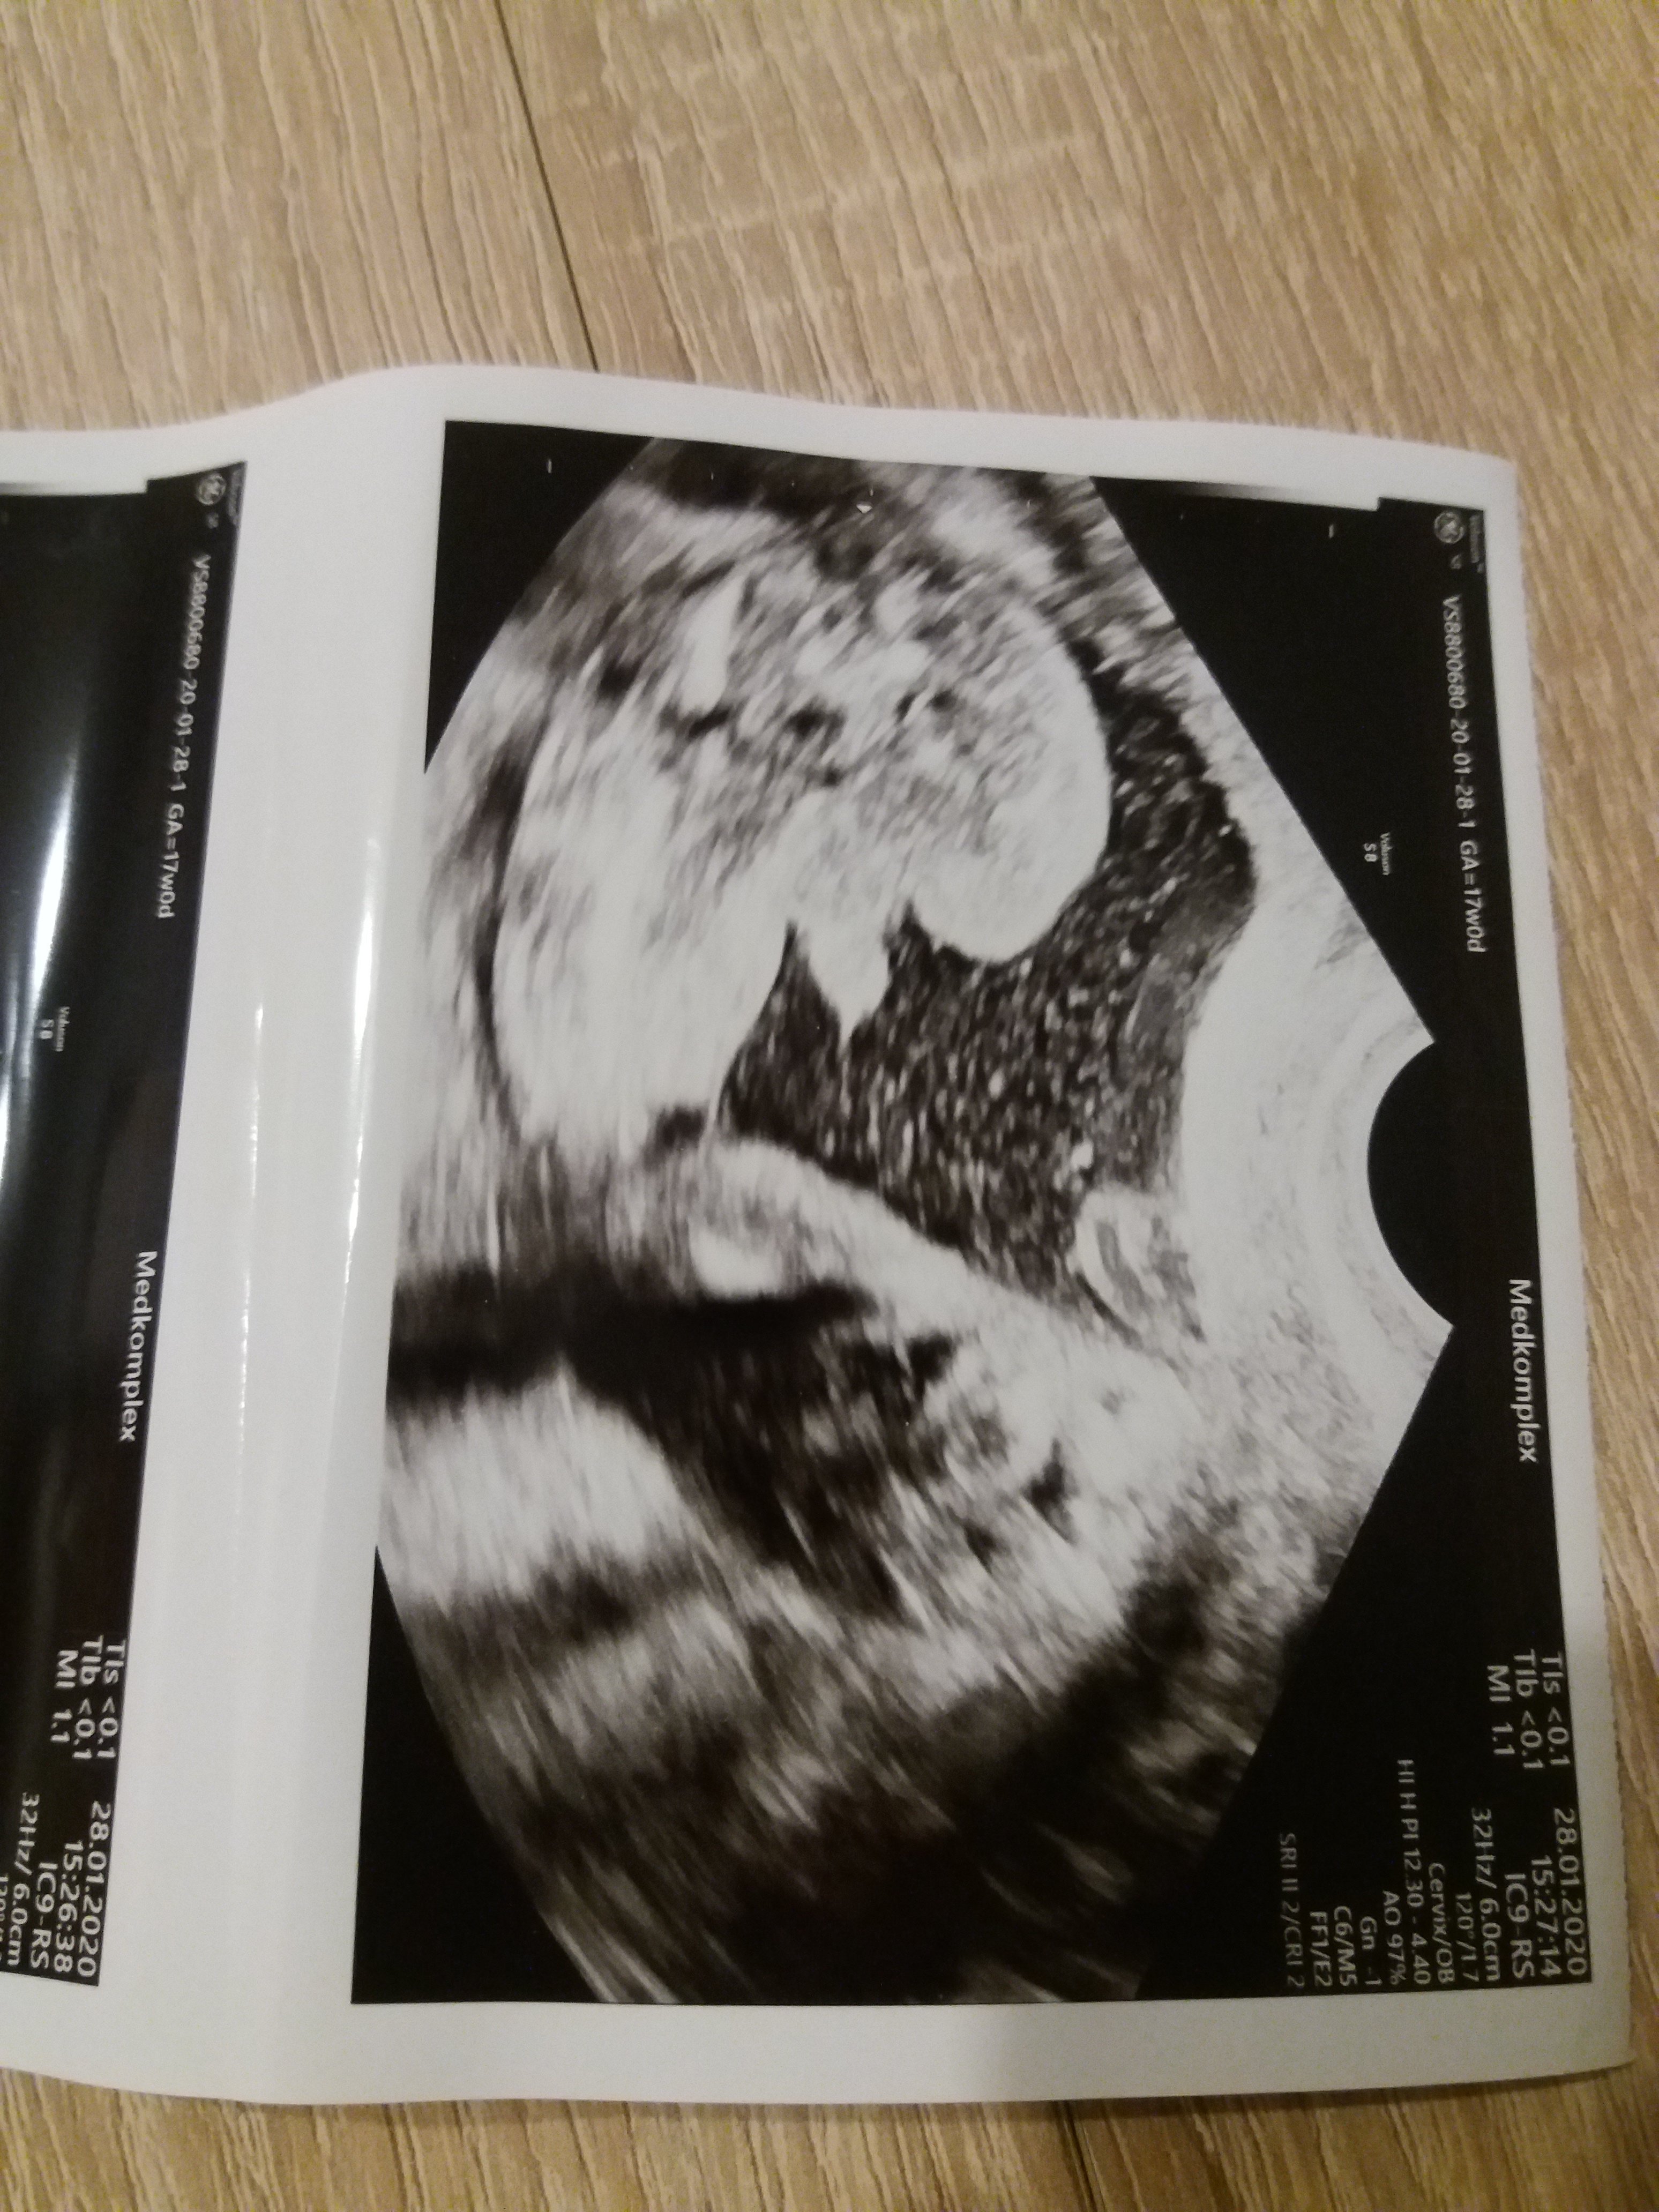

Usg chłopak czy dziewczynka

Witam w 19 tygodniu ciąży dowiedziałam się ze będę miała dziewczynkę w 20 tyg okazało się jednak , że to chłopak. Sama już nie wiem bo na jednym usg widać na pewno dziewuche a na drugim chłopca. Może to pempowina ?? Może ktoś mi pomoże rozwiązać ta zagadkę